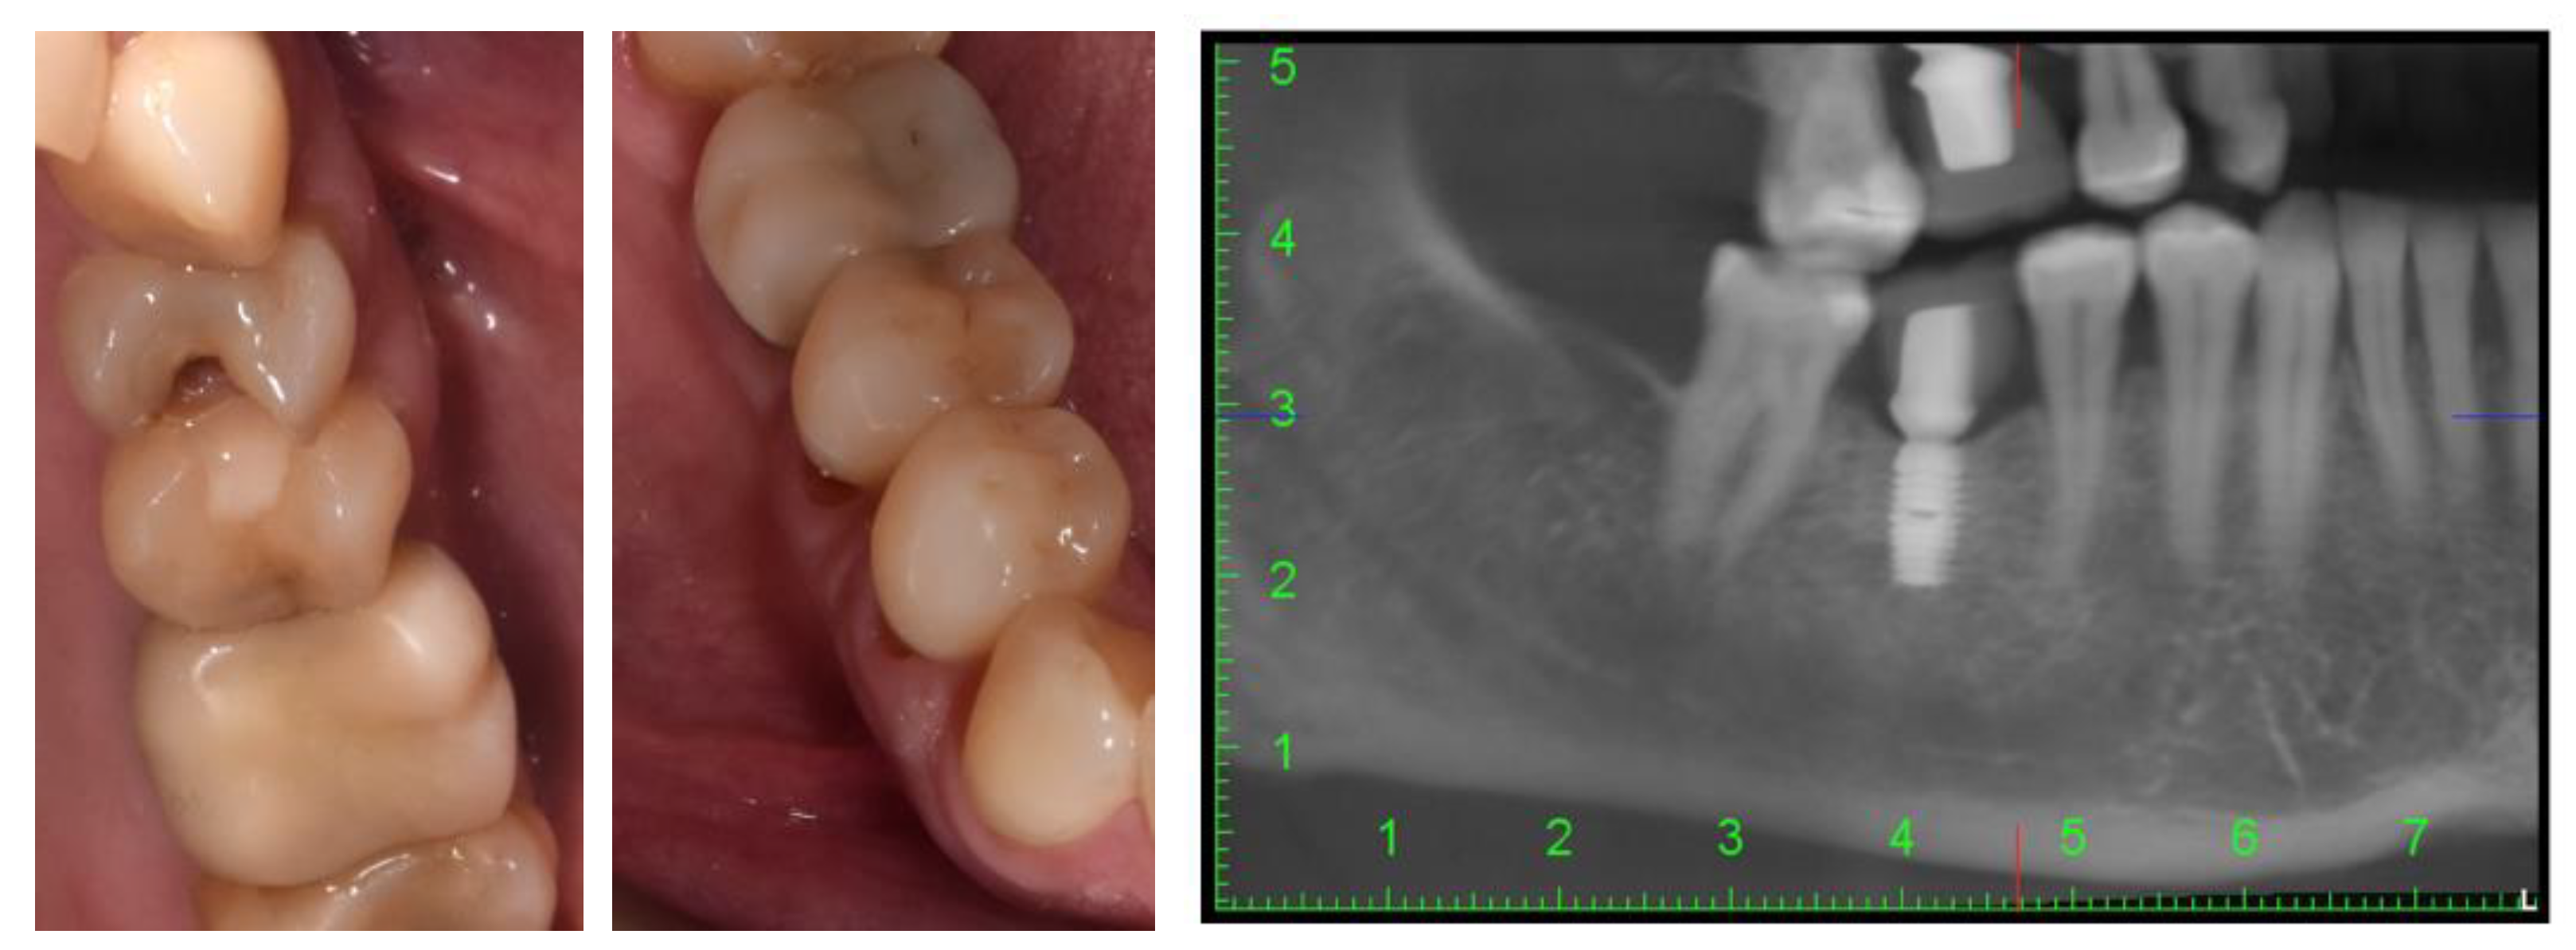

2. Case Description